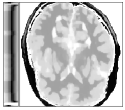

Figure 6 shows examples of the quantitative (magnitude) images of three of the 112 simulated inversion recovery measurements in the test dataset. We also show the regularization parameter-maps for regularization along the spatial directions and along the inversion-time direction generated by the network. The mean PSNR and SSIM of our proposed method is consistently higher for all considered acceleration factors, even compared to PDHG with regularization strength along spatial and inversion-time direction chosen by grid-search with access to the ground truth images (shown in Figure 8 and Table 2). The resulting parameter-maps after performing the regression on the reconstructed images are shown in Figure 7. Again, our proposed method results in the lowest RMS deviation from the ground truth images (Table 2).

CG-SENSE PDHG PDHG PDHG Target/ZF /

Example 1

Example 2

Example 3

CG-SENSE PDHG PDHG PDHG Ground Truth